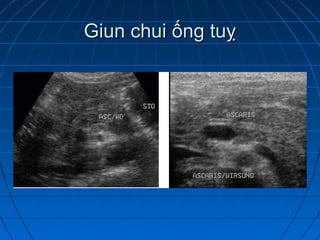

Giun chui đường mậtGiun chui đường mật

Giun chui ống tuỵGiun chui ống tuỵ